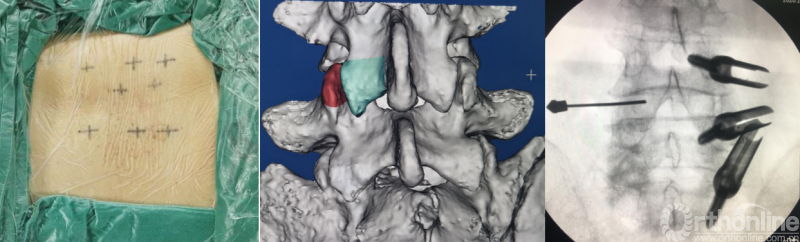

BELIF技术十步法

详细步骤:一定、二剥、三凿、四分、五咬、六切、七牵、八铰、九填、十置

第一步“定”:X线定位在上位椎体下关节突下三分之一部;

第二步“剥”:剥离器+射频剥离、止血、造腔,显露下关节突尖部;

第三步“凿”:凿除部分下关节突;

第四步“分”:分离上关节突及黄韧带;

第五步“咬”:咬除部分上关节突,显露椎间盘及神经根;